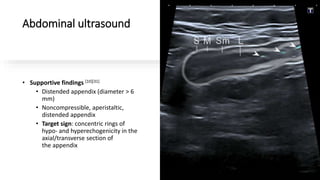

Abdominal ultrasound

• Supportive findings [10][31]

• Distended appendix (diameter > 6

mm)

• Noncompressible, aperistaltic,

distended appendix

• Target sign: concentric rings of

hypo- and hyperechogenicity in the

axial/transverse section of

the appendix